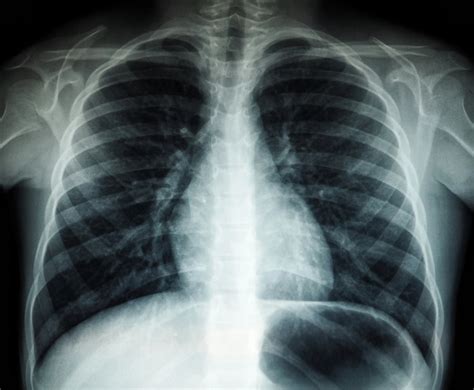

Plaučių uždegimo diagnozė nustatoma įvertinus paciento nusiskundimus, klinikinius simptomus ir atlikus papildomus tyrimus. Pirmiausia gydytojas klausinėja apie ligos eigą, matuoja temperatūrą, įvertina kvėpavimo dažnį, plaučių garsus klausant stetoskopu. Klausant (auskultuojant) plaučius tam tikroje jų dalyje, kur prasidėjo galimas plaučių uždegimas, aptinkami karkalai. Diagnozę galima patvirtinti krūtinės ląstos rentgenograma - tada matomi visi uždegiminiai pakitimai plaučiuose. Jei jų nėra, gali būti, kad pacientas serga bronchitu, kurį taip pat gali sukelti tie patys patogenai.

Pabaigus antibiotikų kursą gydytojas norės įsitikinti, ar jūsų krūtinės ląstos rentgenograma yra normali. Aš jau persirgau plaučių uždegimą - kodėl vėl reikia pas gydytoją? Nors jaučiate, kad savijauta gerėja, tačiau gydymo, nepasitarus su gydytoju, nutraukti nevalia. Neišgydytas plaučių uždegimas - rizika susirgti lėtine plaučių liga. Pas gydytoją būtina atvykti, jei jis patarė tai padaryti arba jei pagerėjus būklei po kiek laiko vėl atsirado kosulys, dusulys ar silpnumo jutimas.